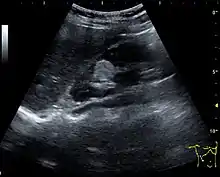

Angiomyolipoma seen as a hyperechoic mass in the upper pole of an adult kidney on renal ultrasonography.